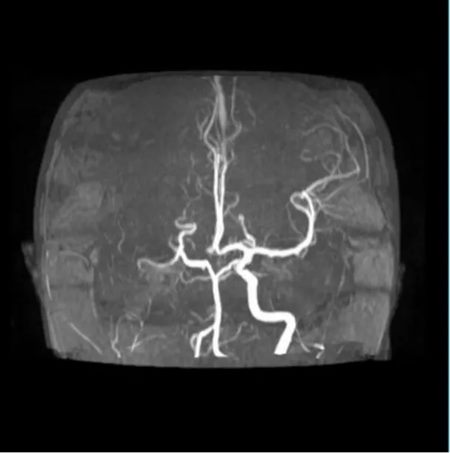

清晨,急诊科送来一名12岁的女孩。突发偏瘫、不能说话——确诊为“急性脑梗死”。

神经内科评估、神经外科接力、影像瞬间出片……

最终决定:脑血管造影 + 经皮颅内动脉取栓术。

手术台上,团队从她堵塞的颈内动脉中,取出一条近10厘米长的血栓。